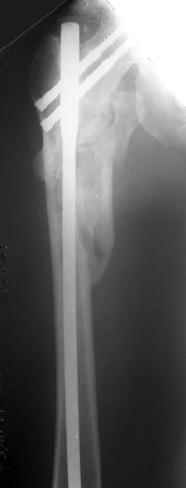

Другое наблюдение:Мужчина, 1957 г.р. Травма в результате ДТП 12.09.04г.

Диагноз: Закрытый оскольчатый подвертельный перелом правой бедренной кости со смещением отломков, оскольчатый перелом большого вертела, отрывной перелом малого вертела.Сопутствующие заболевания: Язвенная болезнь желудка, ремиссия.

Наверно, можно и так сказать, но можно и тоже самое - 4-фрагментный вертельный перелом. Выбор тот же, но с учетом молодого возраста реконструкционный гвоздь тут более применим. Вот уже наш пример.